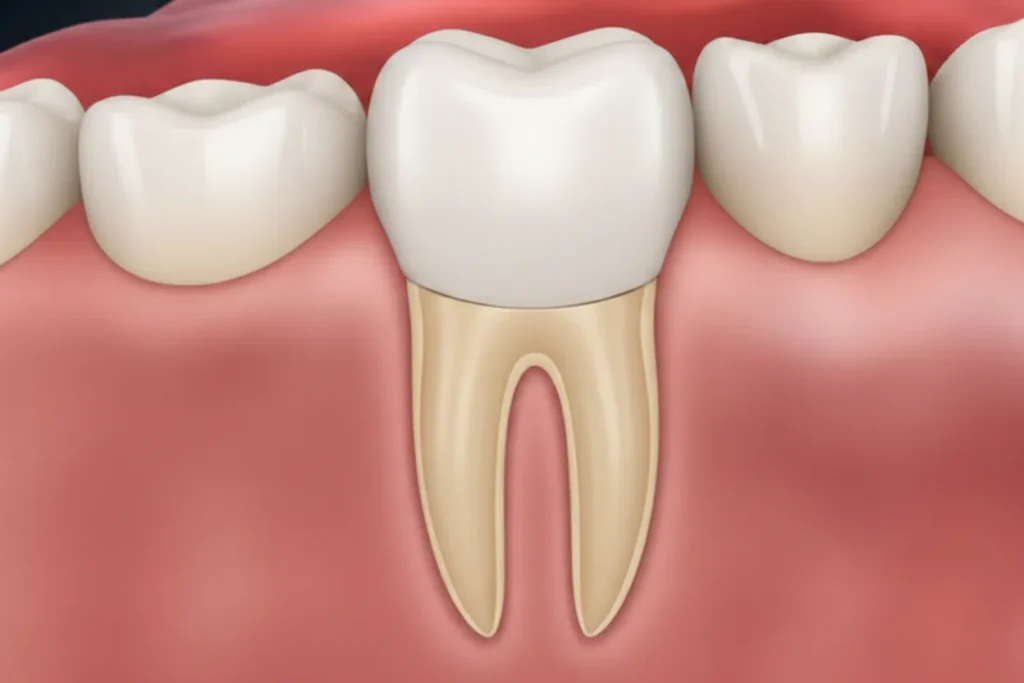

Understand Tooth Anatomy

The Enamel

The Dentin

A sensitive, bone-like layer under the enamel that supports the tooth's structure and surrounds the pulp.

The Pulp

The living core of the tooth containing nerves and blood vessels. This is where root canals treat the infection.